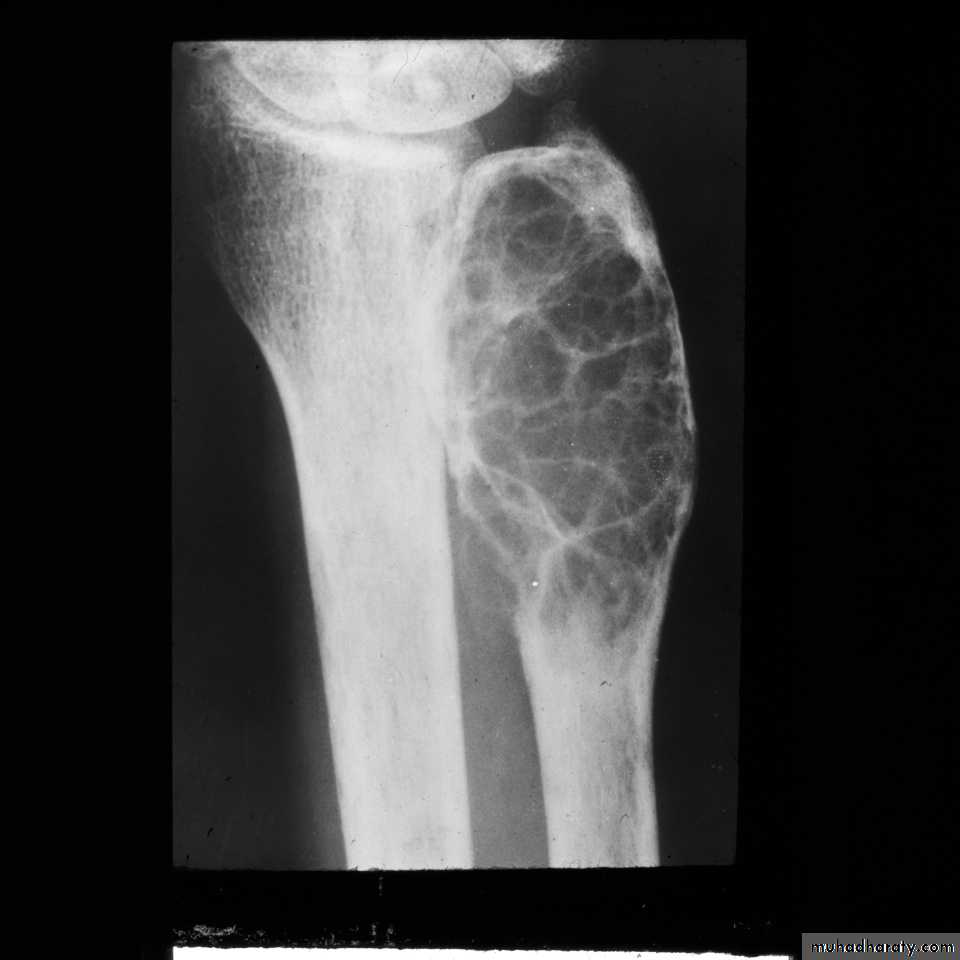

.brown tumour.

Hyperparathyroidism:

Excess parathyroid hormone secretion mobilizes calcium from the bones , resulting in a decrease in bone density , it may be primary from hyperplasia or tumour of the parathyroid glands or secondary to chronic renal failure. generalized loss of bone density.

. subperiosteal bone resorption.